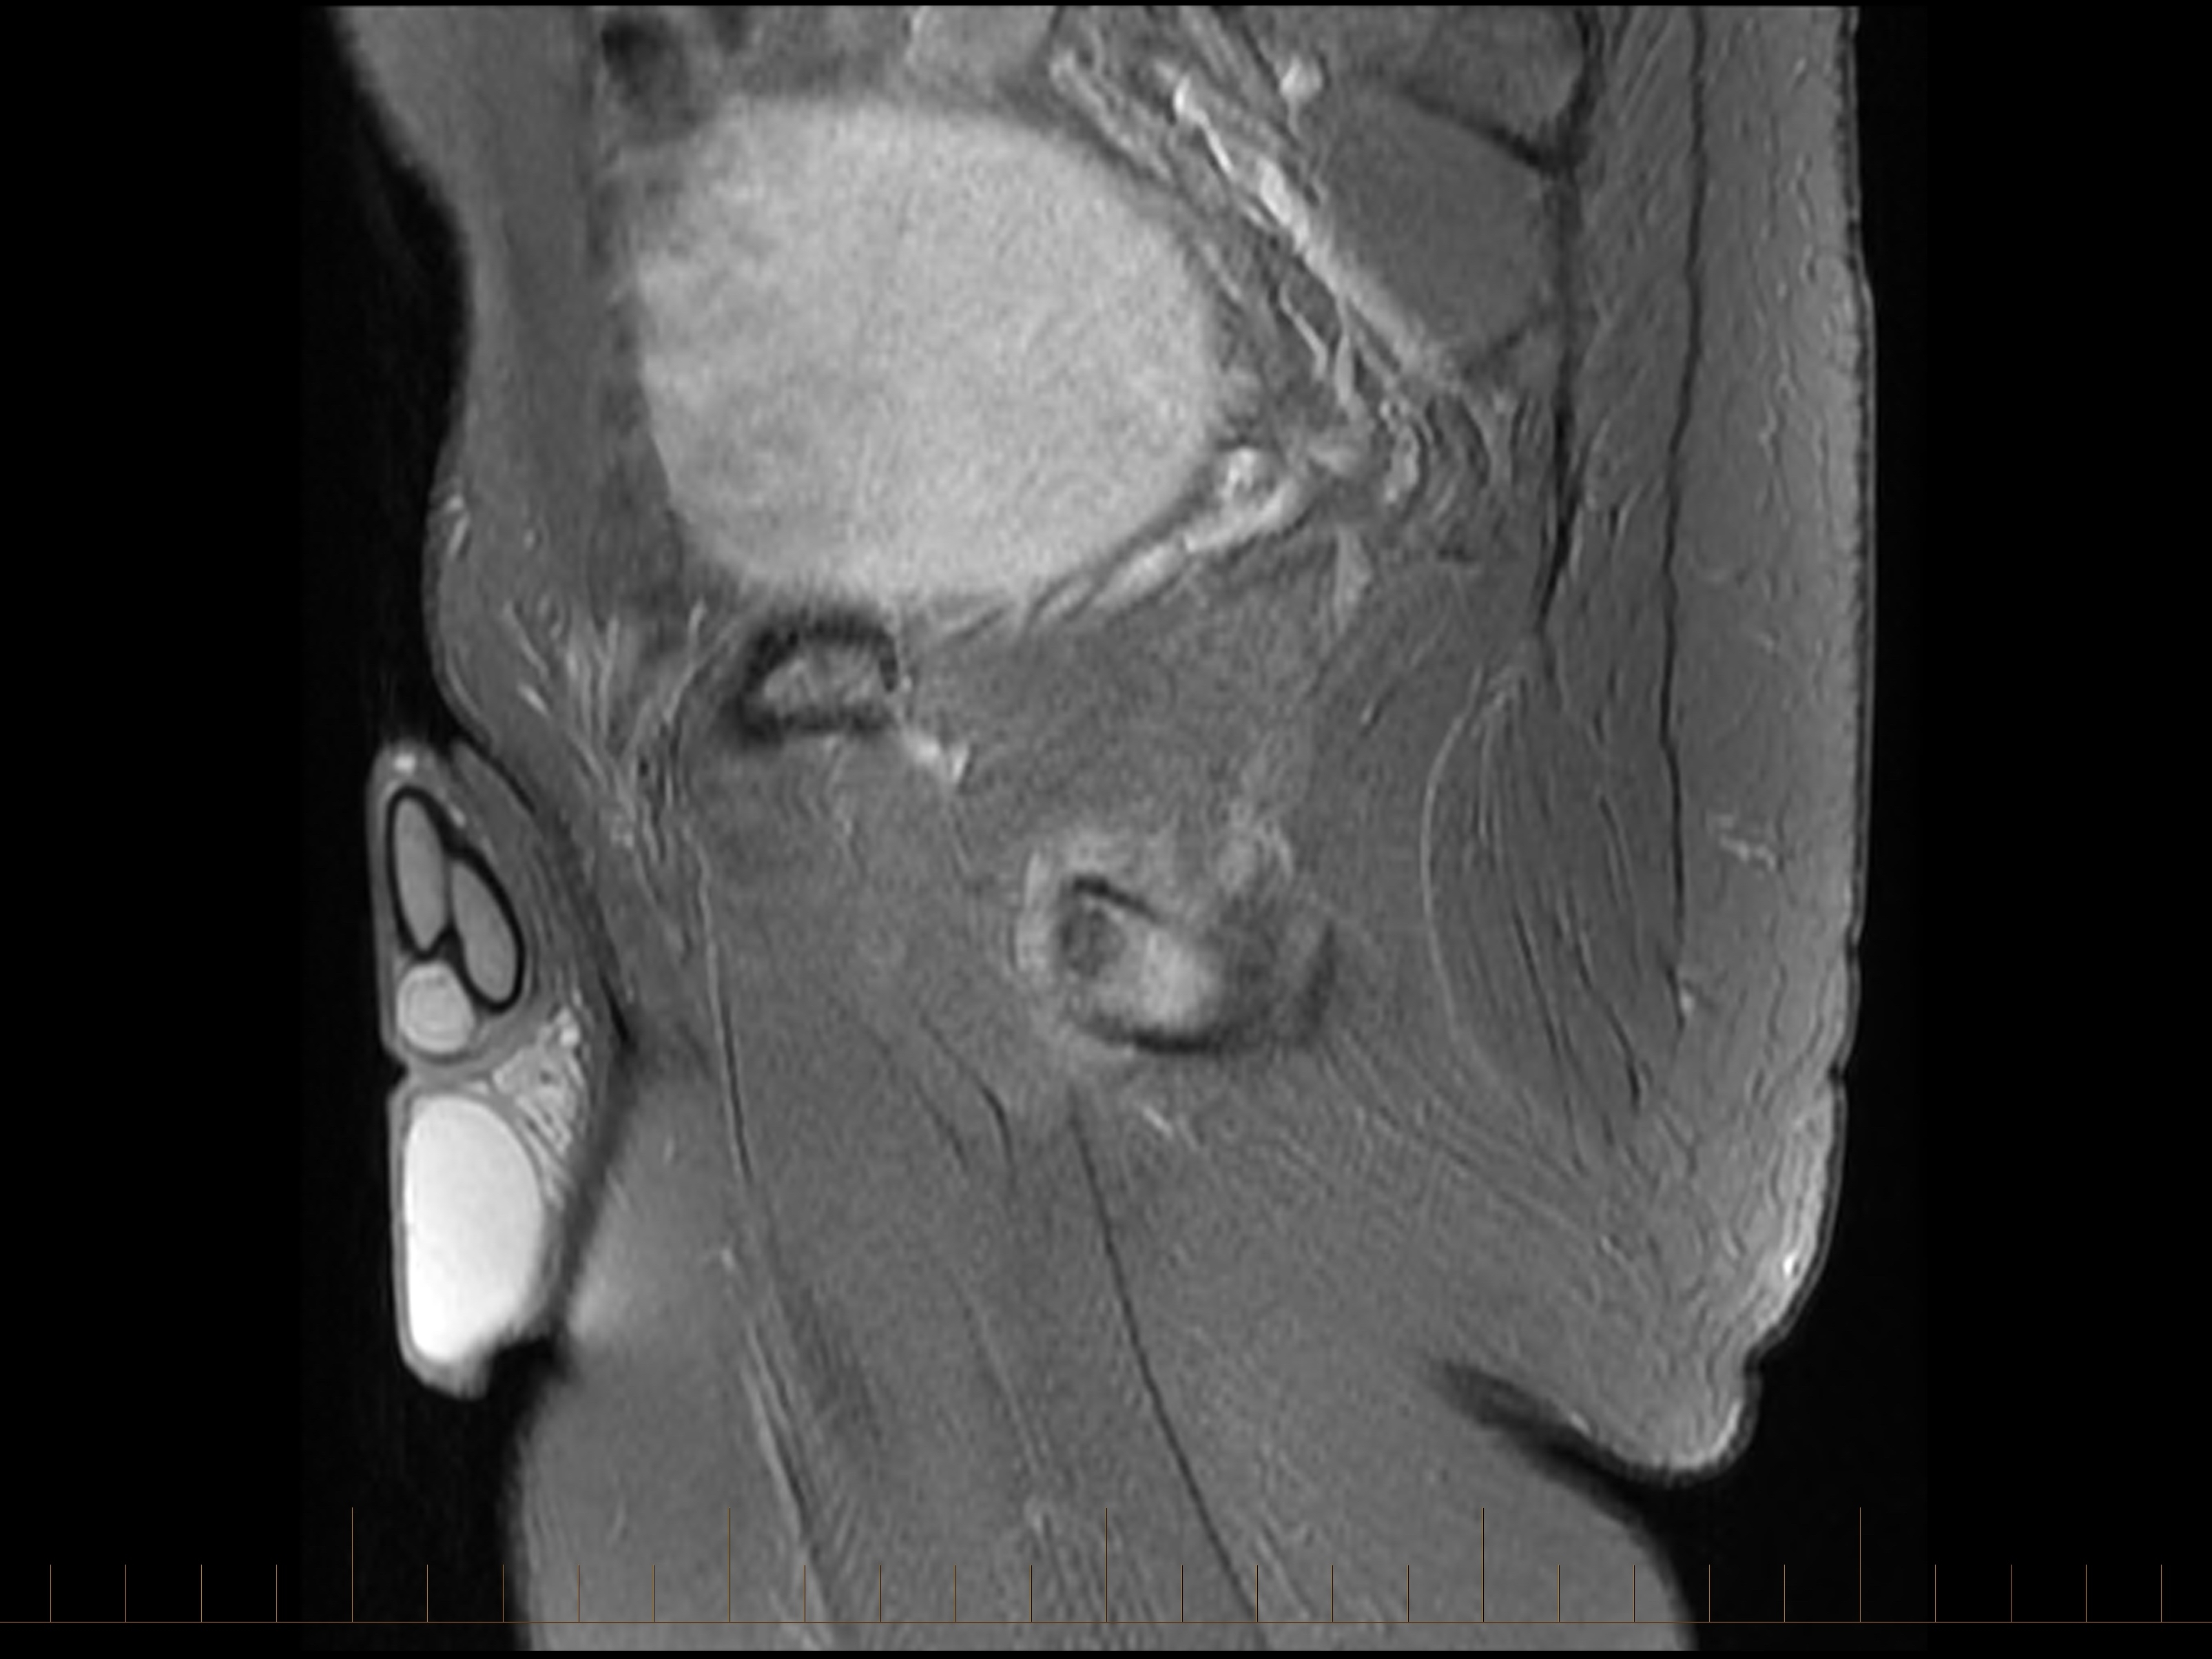

An initial anteroposterior pelvic X-ray demonstrated a visible fracture line in the left interior pubic ramus. While stress fractures in this region are often difficult to see on X-ray imaging, occasionally the fracture line can be clearly identified, as in this case. MRI is particularly useful when the diagnosis is uncertain as it can identify both the fracture line and the surrounding reactive bone changes, helping confirm the diagnosis and assess the extent of injury.